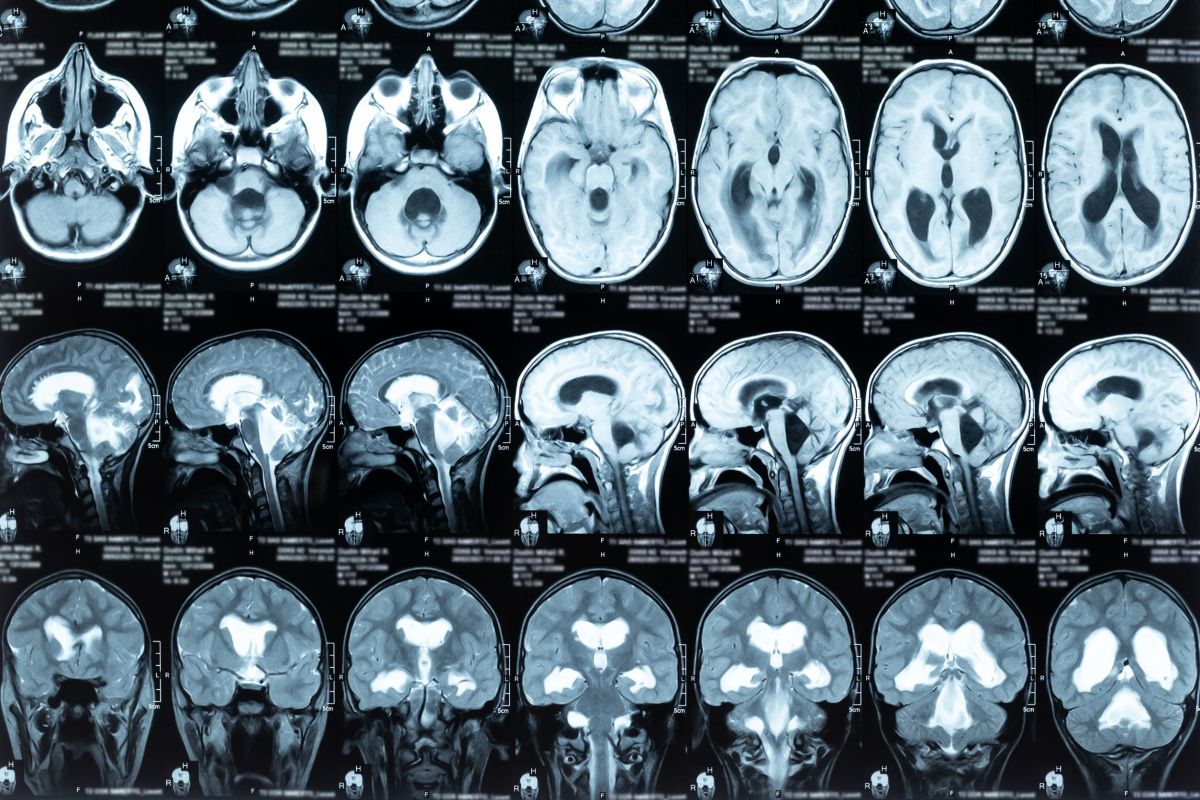

Οι ερευνητές εξακολουθούν να αναζητούν πιθανά αίτια εμφάνισης ακουστικών νευρινωμάτων. Υψηλή δόση ακτινοβολίας κατά την ακτινοθεραπεία του εγκεφάλου, μπορεί να αυξήσει την πιθανότητα εμφάνισης ακουστικού νευρινώματος. Γενικά, δεν υπάρχουν ξεκάθαρα δεδομένα πως περιβαλλοντικοί παράγοντες, όπως τα κινητά τηλέφωνα, μπορεί να προκαλέσουν την εμφάνιση του όγκου. Η αύξηση της συχνότητας εμφάνισης ακουστικών νευρινωμάτων οφείλεται πιθανότατα στην δυνατότητά μας να διενεργούμε περισσότερες και καλύτερες μαγνητικές τομογραφίες, και όχι σε πραγματική αύξηση της συχνότητας του όγκου.

Η τακτική αυτή επιλέγεται σε ασθενείς με μικρούς όγκους ή αυτούς που έχουν αυξημένο κίνδυνο, αν υποβληθούν σε θεραπεία. Επανάληψη των απεικονιστικών εξετάσεων μπορεί να δείξει τον ρυθμό αύξησης μεγέθους του όγκου. Συνυπολογίζοντας τη μεταβολή των συμπτωμάτων, με το πέρασμα του χρόνου, αποφασίζεται το αν θα δοθεί τελικά θεραπεία ή όχι. Σε κάποιους ασθενείς, ο όγκος αναπτύσσεται με τόσο αργό ρυθμό που είναι μάλλον απίθανο να τους δημιουργήσει προβλήματα κατά τη διάρκεια της ζωής τους. Είναι σημαντικό βέβαια, σε όλο το χρονικό αυτό διάστημα της αναμονής, να παρακολουθούνται με επαναλαμβανόμενες μαγνητικές τομογραφίες.

Στερεοτακτική ακτινοχειρουργική μπορεί να χορηγηθεί είτε σε μία δόση, είτε σε 3 έως 5 δόσεις. Η ακτινοθεραπεία προτιμάται για μικρούς και μετρίου μεγέθους όγκους που έχουν την τάση να μεγαλώνουν. Υπάρχουν διάφορες τεχνολογίες στερεοτακτικής ακτινοχειρουργικής. Σε γενικές γραμμές, στόχος της ακτινοθεραπείας είναι η αναστολή αύξησης του μεγέθους του όγκου. Σε μερικούς ασθενείς, ο όγκος μπορεί να διογκωθεί παροδικά μετά την ακτινοθεραπεία, πριν αρχίσει να συρρικνώνεται. Επίσης, μετά την ακτινοθεραπεία, μπορεί να επιδεινωθεί η ακοή των ασθενών. Και με αυτή την θεραπευτική επιλογή, είναι σημαντικό οι ασθενείς να παρακολουθούνται με επαναλαμβανόμενες μαγνητικές τομογραφίες.